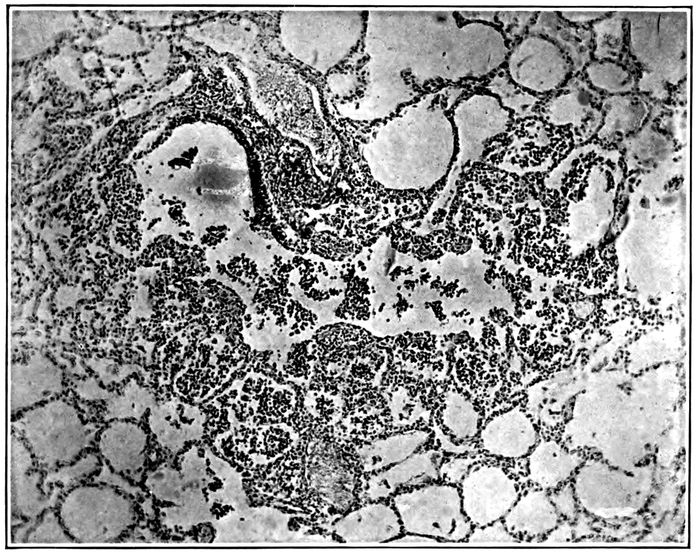

| 2. | Acute bronchopneumonia with nodules of peribronchiolar consolidation and purulent bronchitis | 167 |

| 3. | Acute bronchopneumonia with peribronchiolar consolidation | 169 |

| 4. | Acute bronchopneumonia with peribronchiolar consolidation | 170 |